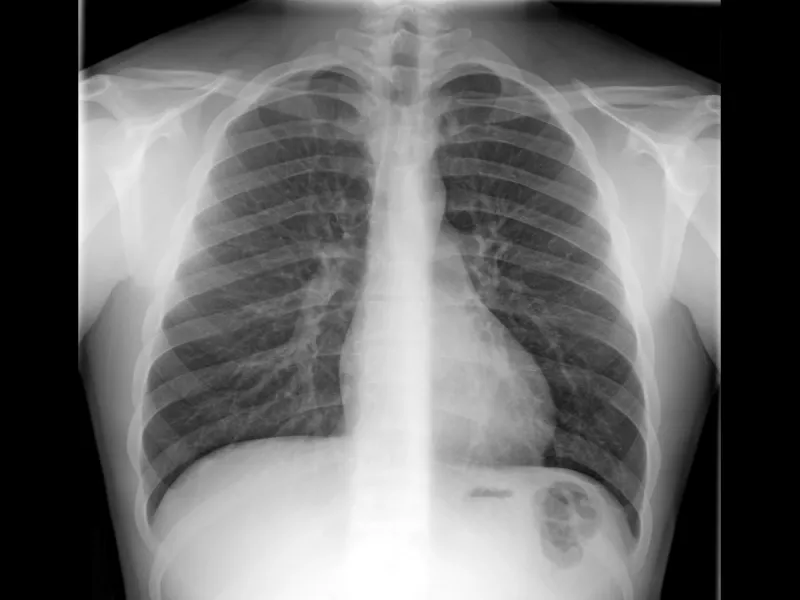

1. Empezá por la base: la radiografía (Rx)

La radiografía suele ser el primer contacto del médico no especialista con la imagen. En el post vas a ver lo esencial: cómo se forma la imagen, qué degrada la calidad y por qué aparecen errores típicos.